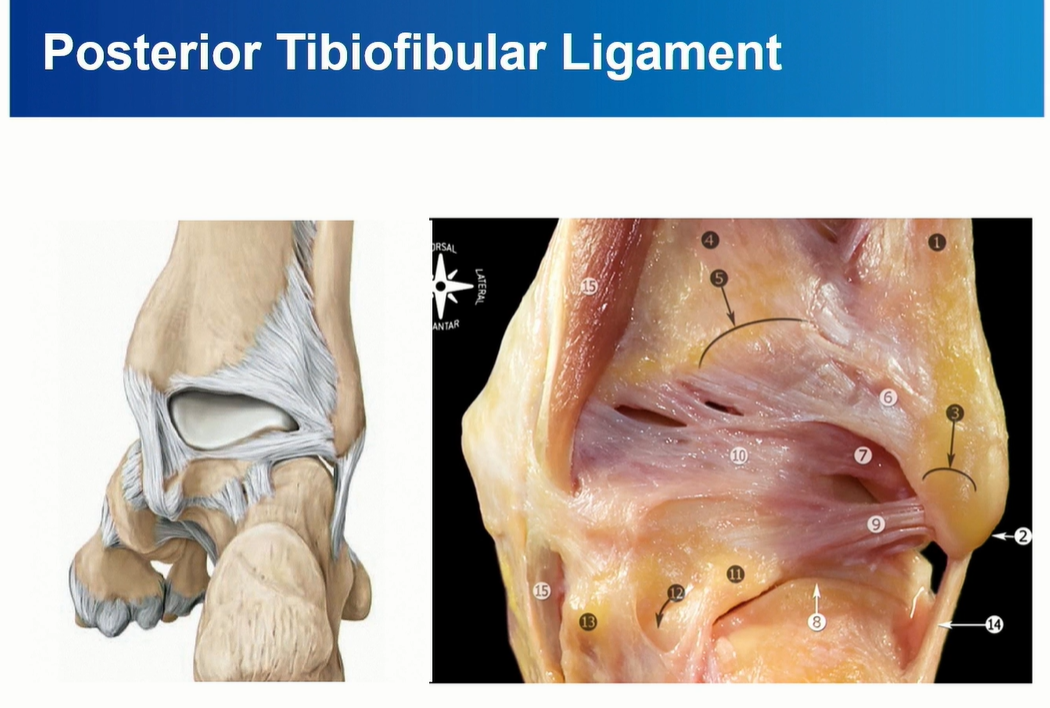

4-3. PITFL

PITFL 은 superfical component와 deep component로 구성된다.

deep component를 inferior transverse ligament라고 부름. 이름대로 horizontal 하게 주행하는 것을 확인할 수 있다.

PITFL은 superficial 과 Deep으로 나누어 보기도 한다.

빨간색으로 표시된 inferior transverse ligament가 아래 쪽에서 주행하는 것을 확인할 수 있다.

파란색으로 표시한 posterior inferior tibiofibular ligment는 위쪽에서 oblique하게 주행하는 것을 확인할 수 있다.

Deep PITFL인 interior transverse ligament는 labrum으로 역할을 한다. 관절면을 deepening 해줌.

intermalleolar ligament는 PTFL 과 Deep PITFL (Inferior transverse ligament)사이에 존재.

비스듬한 주행, Lateral쪽으로 가면서 아래로 주행.